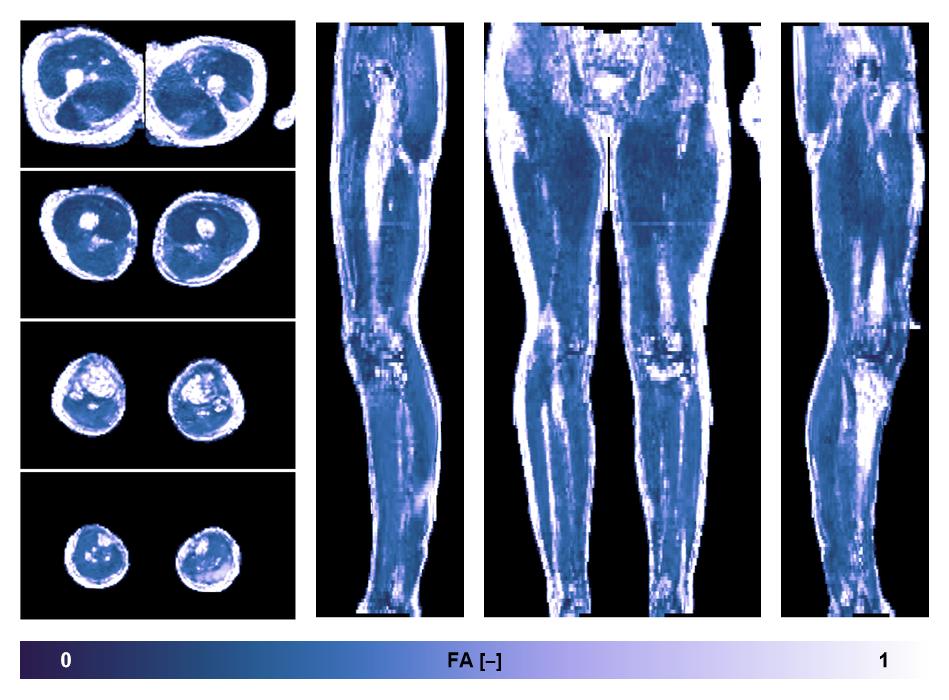

• Fractional anisotropy

IVIM corrected whole leg muscle fractional anisotropy obtained from diffusion tensor imaging.